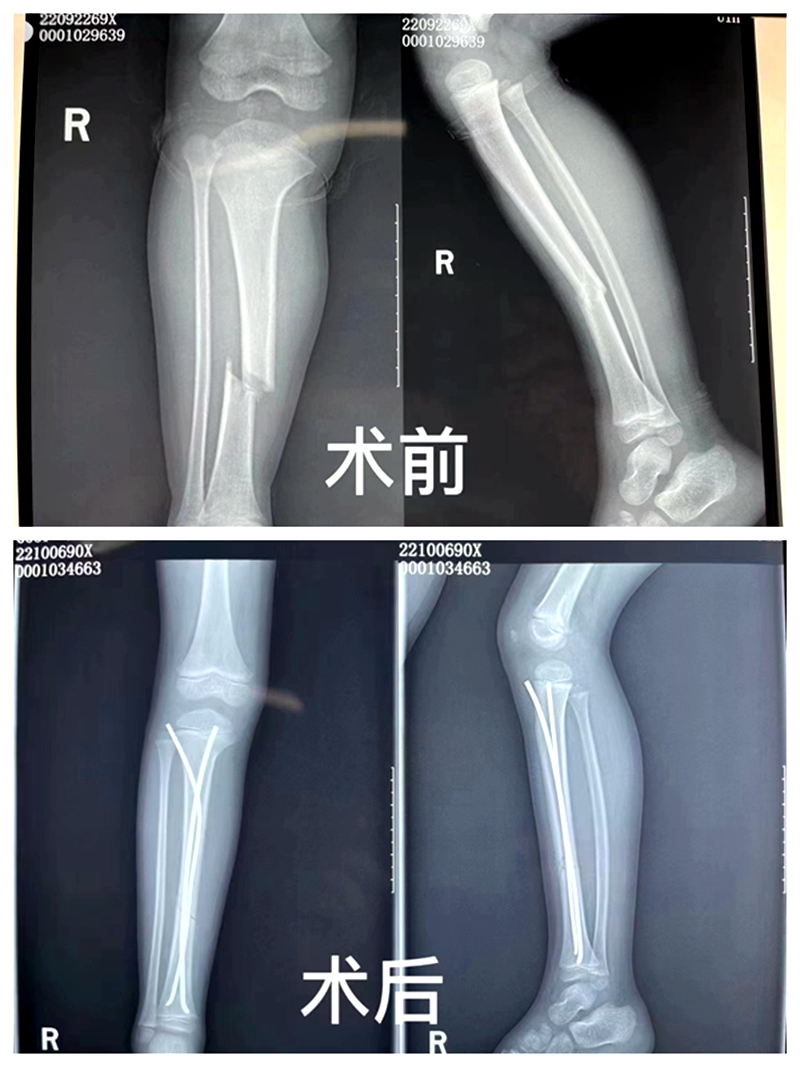

入院后,骨一科副主任高学良,治疗组周正震、祖祎潇医生为患儿进行了详细的查体并完善相关检查,确诊“右侧胫骨干骨折”。考虑患儿年龄小、家属担心术后留疤、传统切开复位内固定手术创伤大、术后并发症多等因素,经骨一科团队周密讨论后,决定行技术难度大,但预后效果好的“闭合复位弹性髓内钉内固定术”。

9月29日,骨一科团队为患儿实施了“右侧胫骨骨折闭合复位弹性髓内钉内固定”术,手术顺利,骨折端对位对线良好,手术切口仅12.5px左右,患儿平稳康复中。弹性髓内钉技术被称为儿童骨科界的一次革命。该项技术利用多点固定的原理,微创、有效地治疗四肢骨折的患儿,是目前儿童长骨干骨折治疗中的主流技术。